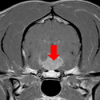

What is Cushing’s disease and how is steroid produced by the body? Hyperadrenocorticism or ‘Cushing’s disease’ is caused by excessive production or administration of steroid. It can be classified as pituitary dependent, adrenal dependent, or iatrogenic. A brief overview of how steroid is produced in the body will help with the understanding of this disease. […]